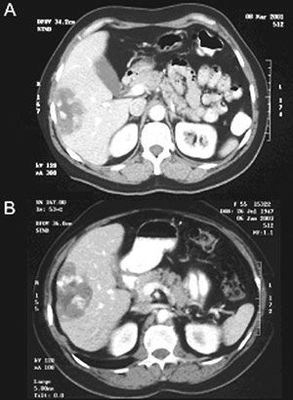

Question 8

Question

En relación con los tumores mucinosos papilares intraductales de páncreas, señalar el enunciado INCORRECTO:

Answer

• Son tumores potencialmente malignos.

• B. Su frecuencia se ha incrementado notablemente en la última década.

• Se distinguen tres subtipos: de conducto principal, de conducto secundario y mixto.

• Deben ser extirpados tan pronto como se diagnostiquen, excepto la variedad de conducto principal.

• Su primera manifestación clínica puede ser un cuadro de pancreatitis aguda.